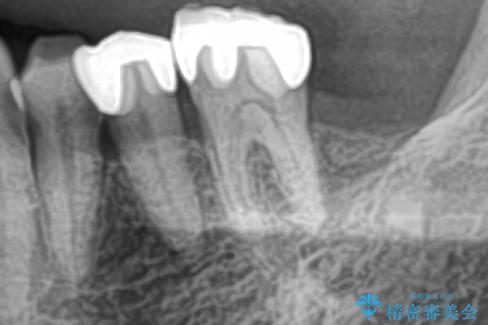

その手前の小臼歯は根尖病変が認められるため根管治療のやり直しからしていくこととしました。

左上の小臼歯は根尖病巣が大きかったため、今後も定期的にレントゲンを撮り、経過観察していく予定です。